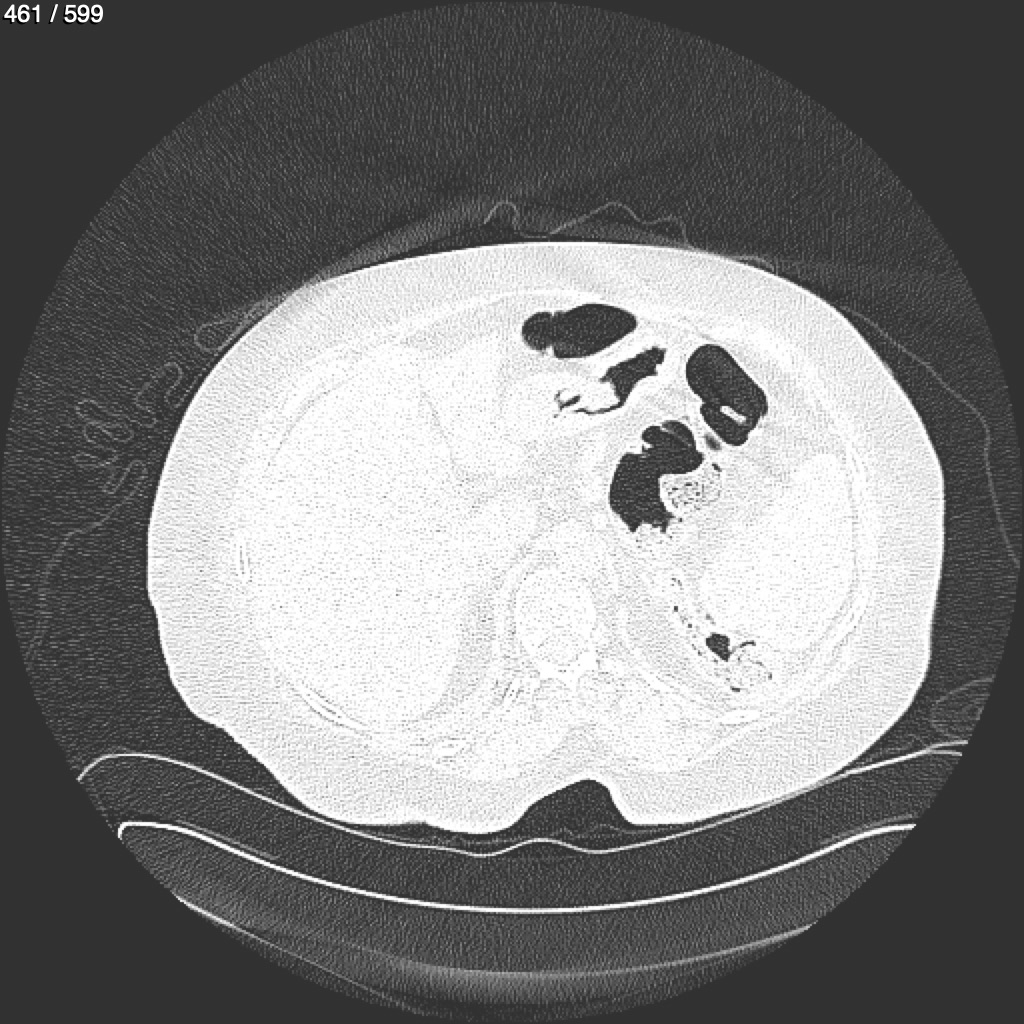

Home G​l​o​r​i​a​ ​G​l​a​d​y​s​ ​B​e​a​s​l​e​y​ ​-​ ​T​ó​r​a​x​ ​T​o​r​a​x​_​S​i​m​p​l​e​ ​(​A​d​u​l​t​o​)